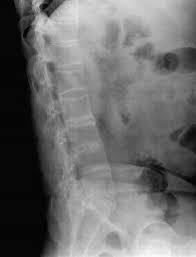

导读: 强直性脊柱炎是一种自身免疫性疾病,可导致反复的腰痛、腰骶部僵硬感等,因此当患者身体转向的时候,就会受到一定的限制,会感觉到很痛很痛。如果疾病继续发展,严重的甚至可导致残疾。

导读: 强直性脊柱炎作为一种人体自身免疫性疾病,如果不及早诊断治疗,就会引起许多的危害,严重的甚至可导致驼背或者残疾。相信大家都不希望自己有驼背现象,那么就要对强直导致驼背有一定的了解,并且要及时治疗。

导读: 强直性脊柱炎发病年龄在15-20岁,开始常表现为下腰痛,疼痛可涉及到臀部或大腿后部,呈发作性,常伴有僵硬。症状沿脊柱向上发展,可达胸廓和肩关节。